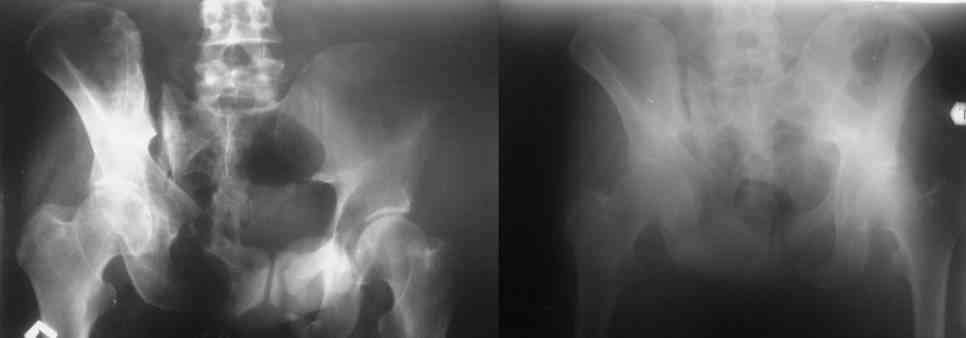

Остается только вариант закрытого аппаратного лечения. В аттаче положение отломков на вытяжении в прямой (АР) проекции. Для сравнения снимок до и во время вытяжения.

> Остается только вариант закрытого аппаратного лечения. В аттаче

К сожалению, аппарат как метод окончательной фиксации застарелых повреждений может не решить проблемы. Аппаратное вправление и удержание зачастую не ведут к образованию прочного сочленения, смещение и нестабильность рецидивируют после снятия аппарата. Это справедливо как для межберцового синдесмоза или акромиально-ключичного

сочленения, так и для лонного или КП. Так что внутреннюю фиксацию надо все-таки подразумевать.

> Остается только вариант закрытого аппаратного лечения.. В аттаче

> положение отломков на вытяжении в прямой (АР) проекции. Для сравнения

> снимок до и во время вытяжения.

Только аппаратными методами в этом случае проблему не решить (фактически вы имеете дело с болтающимися псевдоартрозами), потребуется открытое вмешательство.